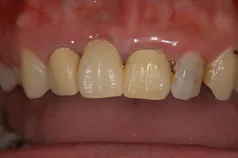

[症例4]

症例3と同様にジルコニア・ブリッジで治療した症例です。

右上中切歯(向かって左上の前歯)が欠損しており、保険のブリッジが入っていました。保険のブリッジは白い部分がレジンという材料でできていますが、経年的に変色するのが大きな欠点です。

治療前は変色があり、歯の長さも不揃いです。

歯の長さがそろうように、歯茎の手術を行い、歯肉がきれいなったあとでジルコニア・ブリッジを装着しています。治療前と比べ、自然で美しい歯になりました。

- 治療期間:6ヶ月

- 治療費:40万円

- 治療回数:18回